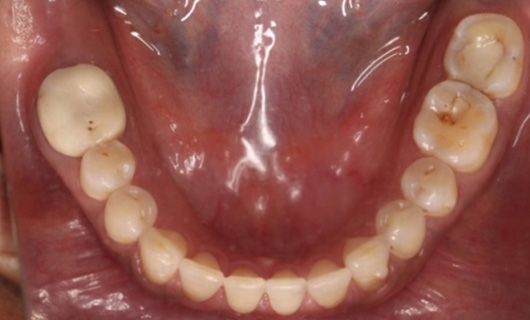

Like braces, Invisalign Braces straighten teeth by placing trays of special material over the teeth in their natural position. A gentle and constant force is used to move the teeth into the desired position without having to go through the hassle of metal wires and brackets. Through digital scanning, they are customized for every patient. Over time, they become a part of the body, since they are so snugly fitting. You are free to eat and drink anything since you will be removing all foods before every meal.